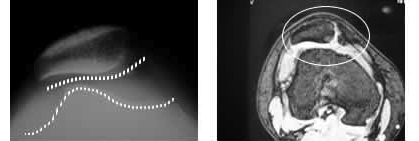

レントゲンにて、脱臼時は膝蓋骨が大腿関節面の外側に脱転している像が見られ、亜脱臼では脱転が完全でなく、大腿骨外側に引っかかったり変位していたりする像を呈します(写真1)。強い外力によって発生した場合は、脱臼骨折となり骨軟骨片が存在します。膝蓋大腿関節の適合性不良も確認できます。MRI(写真2)では軟骨変性像、関節面の適合性不良(CTでも)、周囲軟部組織の介在、関節水腫像などを呈します。

写真1・2

左:レントゲン像(軸写):膝蓋骨は亜脱臼して外側に変化している。関節の適合性悪し

右:MRI:関節の適合性が悪く、関節面の信号変化、関節水腫(白色)を認める